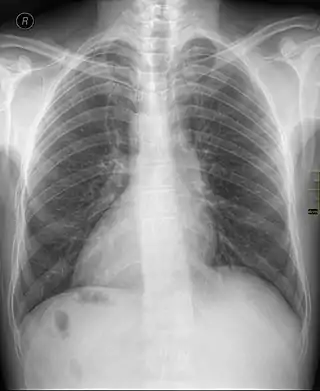

Dextrocardia (from Latin dextro, meaning "right hand side," and Greek kardia, meaning "heart") is a rare congenital condition in which the apex of the heart is located on the right side of the body, rather than the more typical placement towards the left.[1][2]

Medical diagnosis of the two forms of congenital dextrocardia can be made by ECG[3] or imaging.